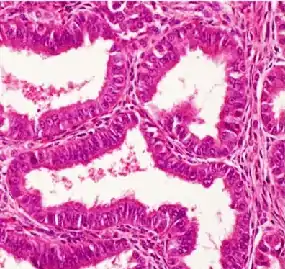

![]() Histopatología de un adenocarcinoma endometrioide bien diferenciado en el ovario | ||

La microscopía óptica muestra glándulas tubulares, parecidas al endometrio[7]